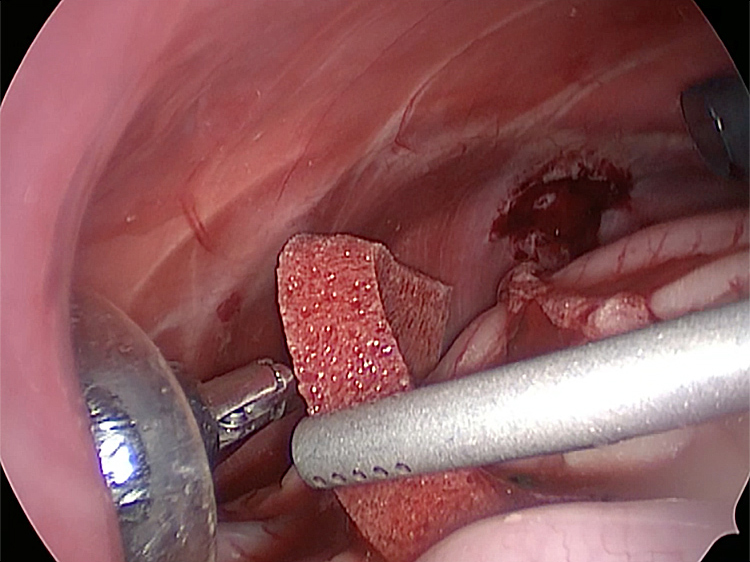

このときに胆嚢と一緒にクリップやガーゼも回収します。そしてお腹の中をきれいにしていきます。

最後にお腹の中をきれいに洗浄していきます。

お腹の中を洗浄して終了となります。